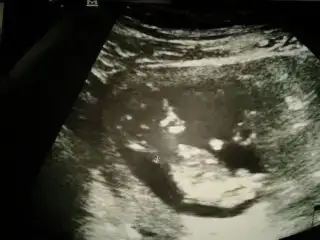

$IMG_0799.webp $IMG_0800.webp $IMG_0801.webp $IMG_0798.webp Merhaba arkadaşlar bende aranıza yeni katıldım.12 Haftalık hamileyim konuyu okuyunca dayanamadım yükledim resimleri.Bakarmısınız sizce ne olabilir bebişimin cinsiyeti

Kızlar fotograflar net deil doktorumuz bu konuda çok iyi değil güzel resim çekemiyor :1: ama gördgüğünüz kadarıyla tahmin söylersniz sevirinim :40::40: tşk :46: